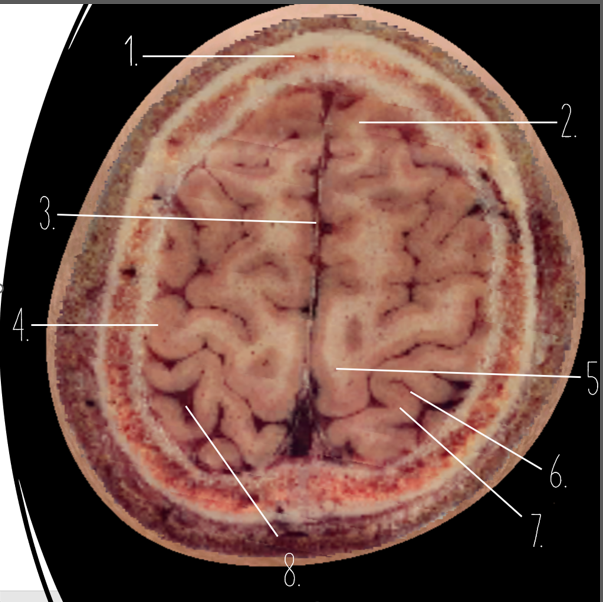

Brain Cross Sectional

1

Frontal Bone

2

Frontal Lobe

3?

Falx Cerebri

4?

Gray Matter

5?

White Matter

6?

Sulcus

7?

Gyrus

8?

Fissure